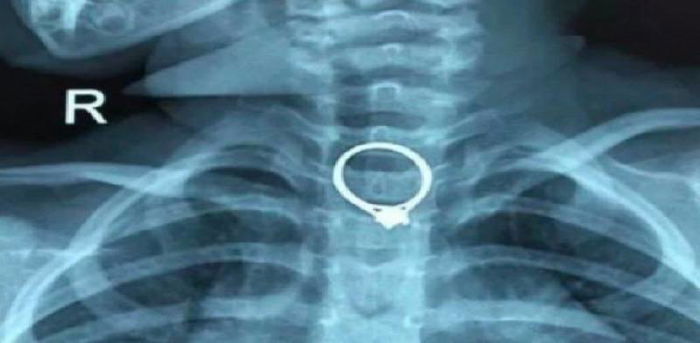

anak tertelan cincin

Screenshot: SOHU News

Ibunya yang risau bergegas membawa anaknya ke Hospital Zhuhai. Doktor di hospital tersebut akhirnya berjaya mengeluarkan cincin berlian berukuran 2.35cm kali 2.04cm, selepas 30 minit pembedahan.

Ini bukan pembedahan pertama anak tertelan objek yang pernah berlaku. Jadi pihak hospital mendesak ibu bapa untuk lebih berhati-hati dan jangan biarkan anak bermain dengan objek kecil.